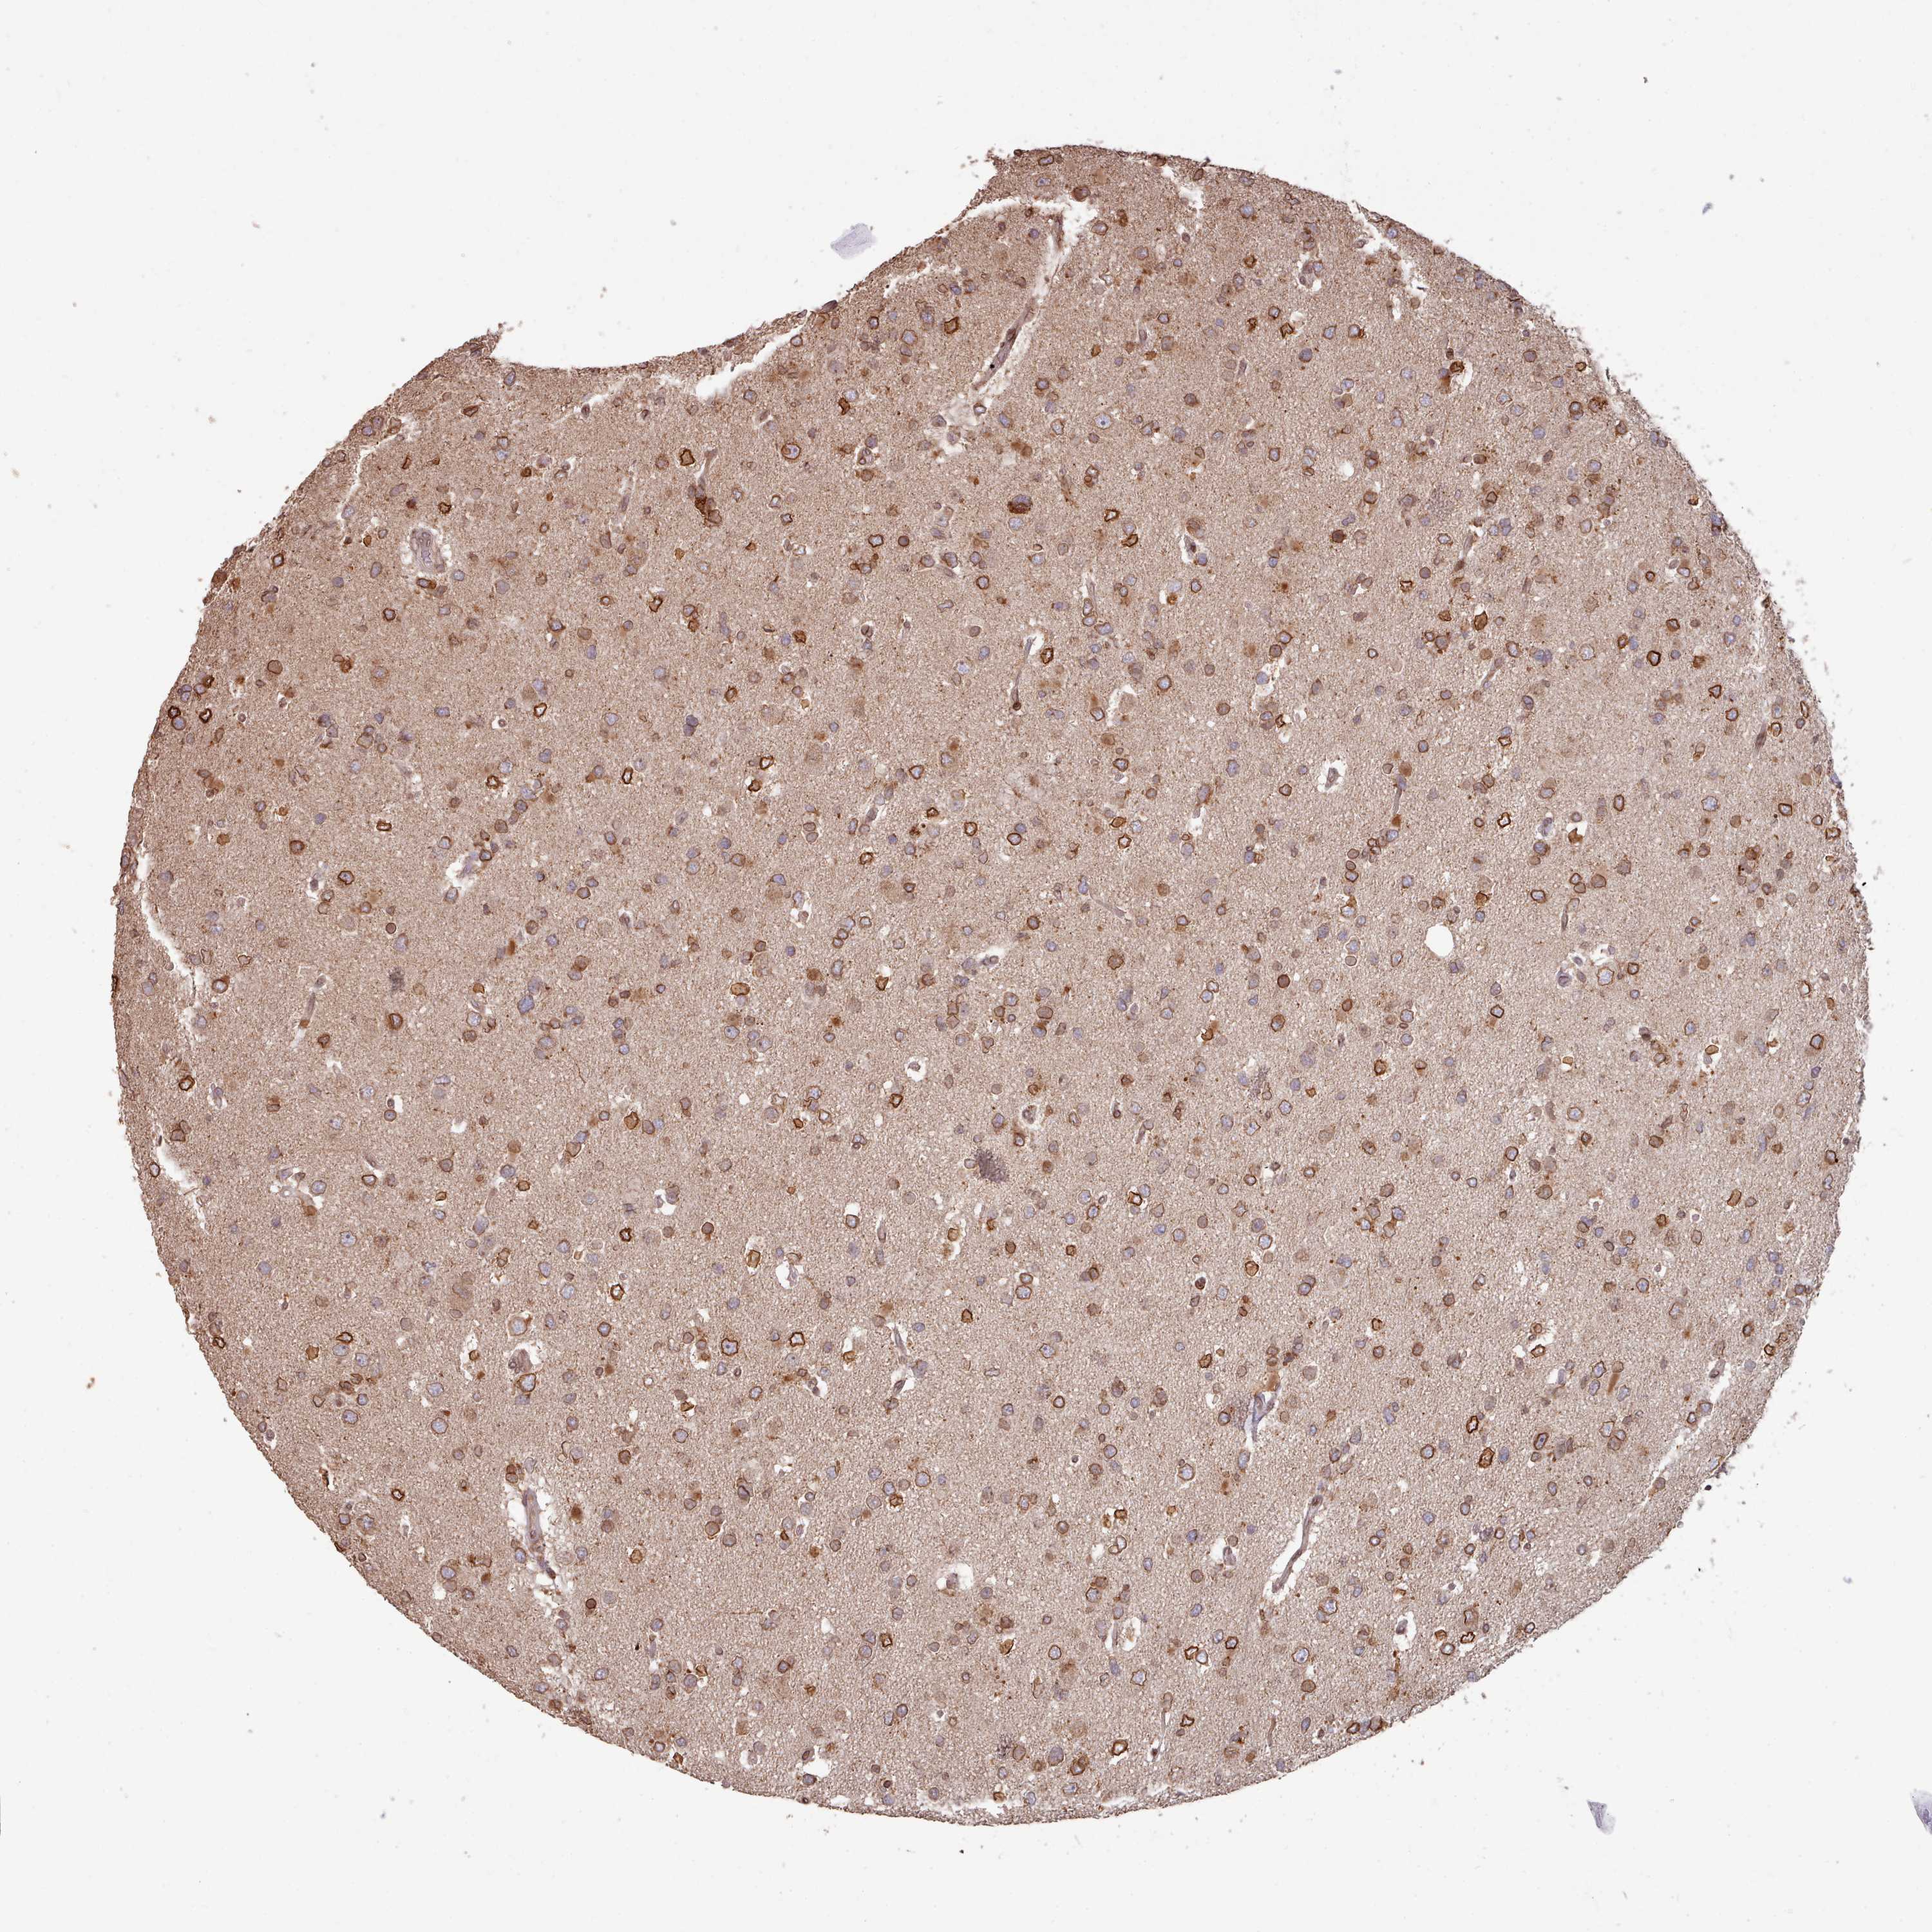

GLIOMA - Protein expressioni

A mouse-over function shows sample information and annotation data. Click on an image to view it in a full screen mode. Samples can be filtered based on level of antibody staining by selecting one or several of the following categories: high, medium, low and not detected. The assay and annotation is described here.

Note that samples used for immunohistochemistry by the Human Protein Atlas do not correspond to samples in the TCGA dataset.

Antibody stainingi

Antibody staining in the annotated cell types in the current human tissue is reported as not detected, low, medium, or high, based on conventional immunohistochemistry profiling in selected tissues. This score is based on the combination of the staining intensity and fraction of stained cells.

Each image is clickable and will lead to virtual microscopy that enables deeper exploration of all samples and also displays staining intensity scores, fraction scores and subcellular localization as well as patient and tissue information for each sample.

Antibody HPA047151

Antibody HPA050546

Antibody HPA070991

Staining

High

Medium

Low

Not detected

Intensity

Strong

Moderate

Weak

Negative

Quantity

>75%

75%-25%

<25%

None

Location

Nuclear

Cytoplasmic/membranous

Cytoplasmic/membranous,nuclear

Glioma, malignant, High grade

Glioma, malignant, Low grade